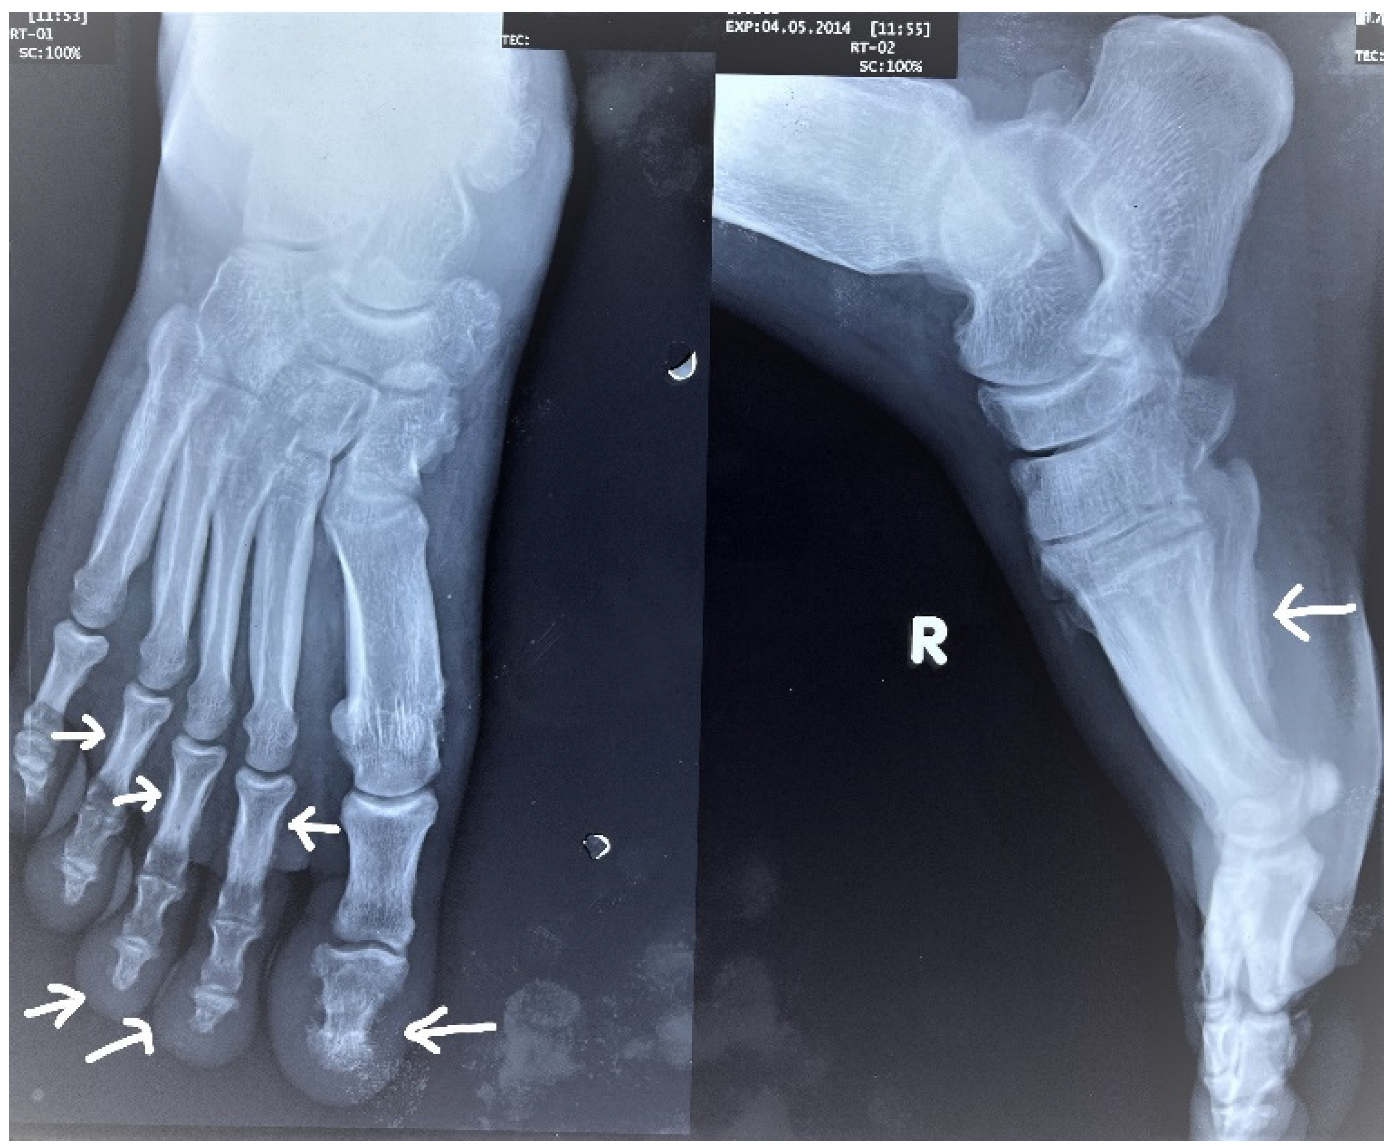

2. Case Report